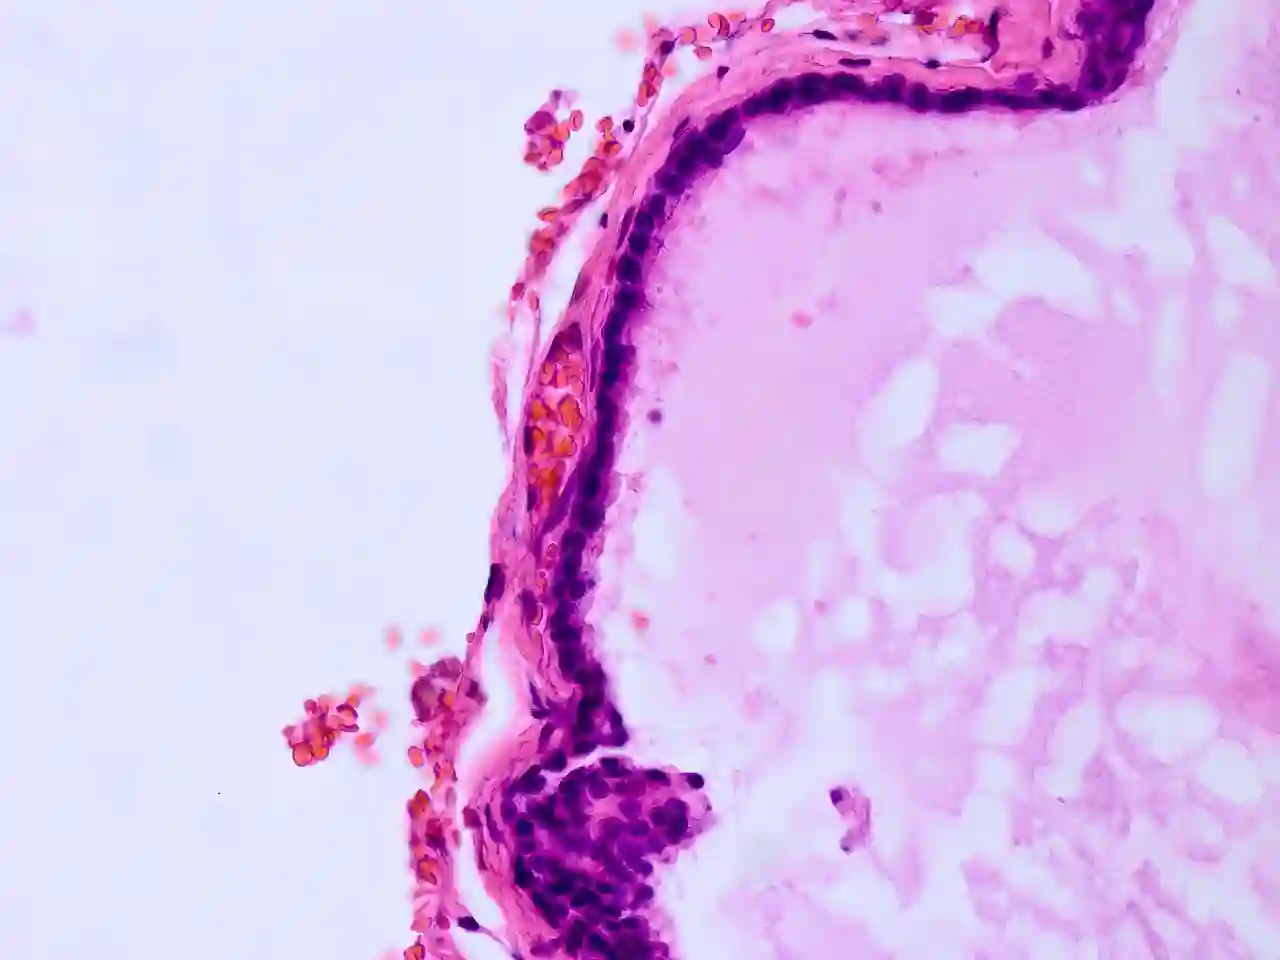

Histopathologie